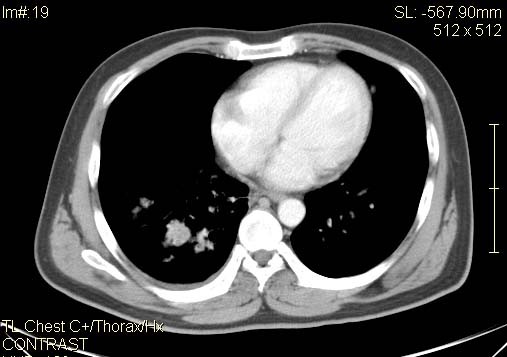

以下是引用qc80012345在2007-4-17 12:33:00的发言:[br]右肺下叶周围型肺癌伴肺门及纵隔内淋巴结转移;比较清楚。

以下是引用qingyuan在2007-4-17 14:19:00的发言:[br]右肺下叶外侧后段胸膜下区节结样病变、分叶、内可见空洞,壁厚薄不均,胸膜凹陷、肺门周围区纹理增粗、僵硬、并近似小结节样改变,肺门区软组织节结、纵膈淋巴结肿大,患者病史长、抗炎治疗无好转炎性改变基本排除,考虑:右肺下叶周围型肺癌伴纵膈及右肺门区淋巴结转移、肺内淋巴管受侵。